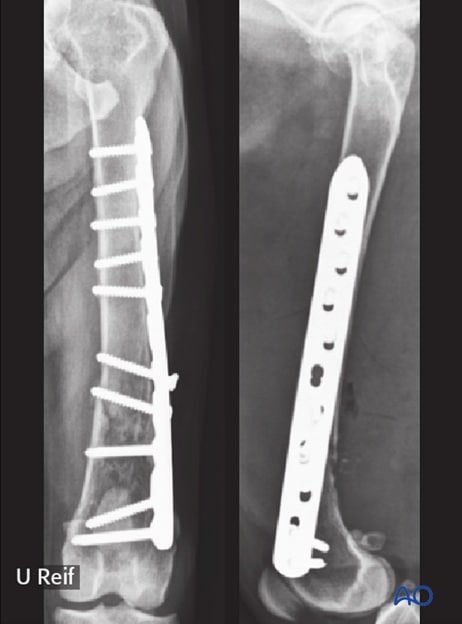

Surgical procedures

Surgical procedures involve the use of tools to fix the bones with the help of plates or screws. Other medical equipment is used to give proper alignment to the bones. This helps in the proper functioning and healing of the fracture.

Open fractures need proper healing and immediate attention. It needs medicines along with the surgical procedures. It also requires proper care for the dog after the surgery.

Complications can also occur and cause misalignment. It can further cause issues if not managed properly. Infections can also come post-surgery, and implant failures can also happen.